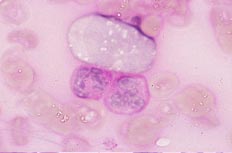

[骨髄×1000.MG染色] 芽球様細胞は核形不整が顕著で核小体が著明である. |

| [骨髄×1000.MG染色] 芽球様細胞は好中球よりも大型である. |

[骨髄×1000.MG染色] 芽球様細胞おける細胞質の好塩基性は中等度から強度で、空胞が目につく. |